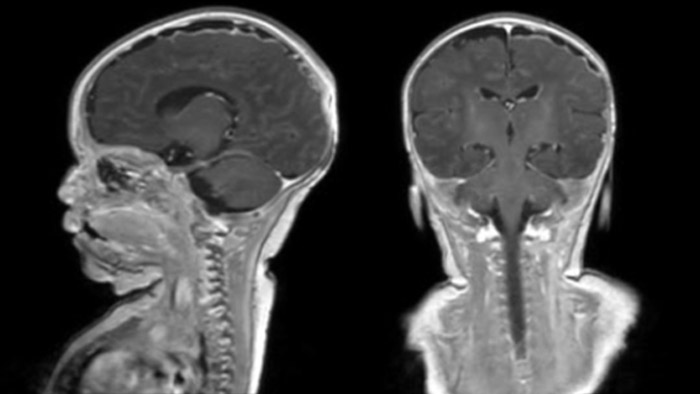

Rostral meningitis and arachnoiditis Both images are from the same 3D T1-weighted post contrast sequence in a newborn, under treatment.